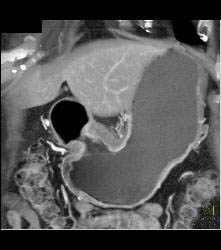

Antral Carcinoma